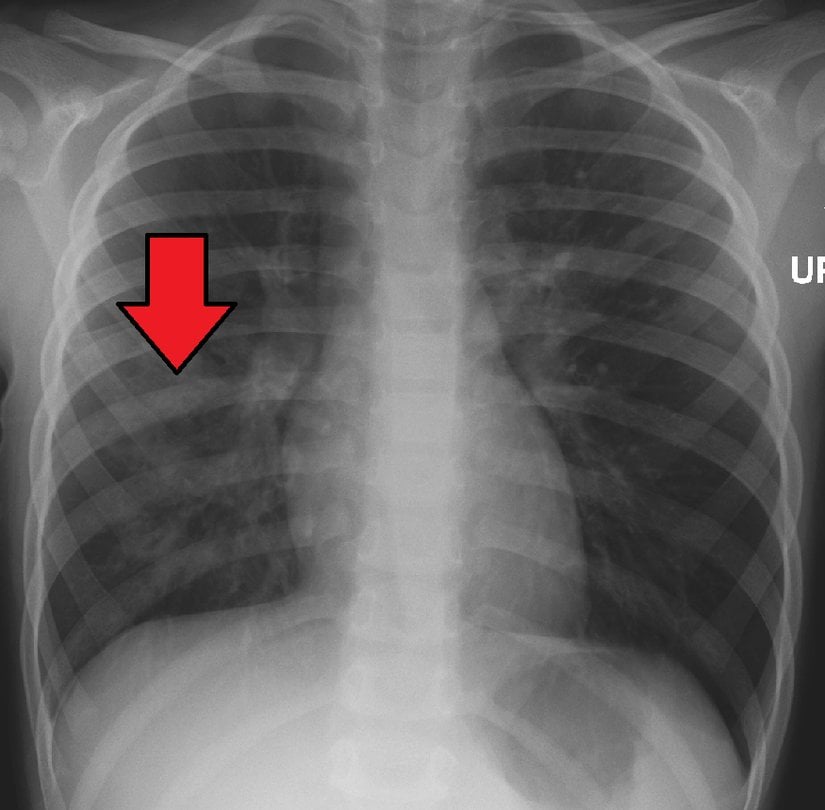

Buna bağlı olarak ateş çıkar, soğuk titremeler yaşanır ve bakteriyel zatürrede yaygın olarak görülen bitkinlik oluşur. Bakteriler, nötrofiller ve civardaki kan damarlarından sızan sıvılar, zatürreye ait tipik göğüs X-ışını taraması fotoğraflarındaki bulutlu görünüme neden olur:

İlk muayeneden sonra hekimin şüphe etmesi halinde göğüs X-rayi, kan testi ve sputum örneği test edilerek teşhis kesinleştirilir. Gerekli görülmesi halinde nabız oksimetrisi ile kandaki oksijen seviyeleri de kontrol edilir. Çocuklarda, yukarıda sözünü ettiğimiz nefes sıklaşmasına dikkat edilmelidir. Stetoskop yoluyla yapılan dinlemelerde hırıltılar duyulabilir.

Tedavi edilmesi halinde birçok zatürre tipi 3-6 gün içinde kontrol altına alınabilmektedir. Tüm semptomların ortadan kalkması ise birkaç hafta sürebilir. Çoğu zaman X-ışını görüntülerindeki bulgular 4 haftada yok olur ve hastalığın öldürücülük oranları oldukça düşüktür (%1 civarındadır). Yaşlı ve savunma sistemi zayıf kişilerde tam iyileşme 12 haftayı bulabilir.